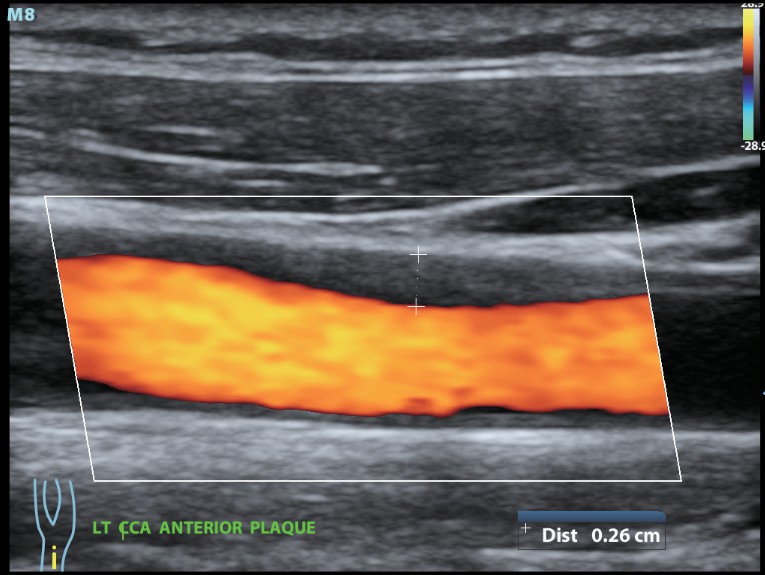

Клинические изображения